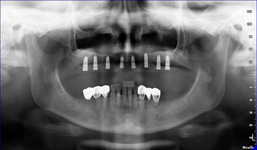

Zásadním faktorem pro úspěšné ošetření je přesná a detailní diagnostika a dokonalé naplánování celého ošetření. K tomu vždy využíváme kombinaci zjištění z klinických vyšetření a rentgenologických dat, které následně zpracováváme v plánovacím softwaru.

Jak pro ošetření stomatochirurgická tak implantologická spolu různými dostavbami kosti je vždy nutné předem znát umístění důležitých anatomických struktur (cévy, nervy, čelistní dutiny). Naše pracoviště jako první v České republice začalo

od roku 2004 používat speciální digitální zubní tomograf 3D DVT NewTom a dále také využíváme nejnovější hybridní CBCT (3D) + 2D přístroj NewTom GiANO, které umožňují 100% diagnostiku množství a kvality kosti a veškerých důležitých anatomických struktur.

Pomocí tohoto přístroje je možné zjisti skutečnou situaci v čelistních kostech pacienta tedy množství kosti - můžeme změřit skutečnou šířku i výšku kosti, i kvalitu kosti (hustotu) v místě uvažované implantace. 3D (tříprostorové) zobrazení umožňuje

Lékař si vytvoří všechny typy zobrazení potřebných pro naplánování – tedy 2D snímky (panoramatický), příčné řezy i 3D model.

Vidí zde i důležité anatomické útvary – čelistní dutinu, průběh nervu atd. Po proměření množství kosti – šířky i výšky vybere z databáze vhodný typ implantátu a umístí ho do požadované lokality.